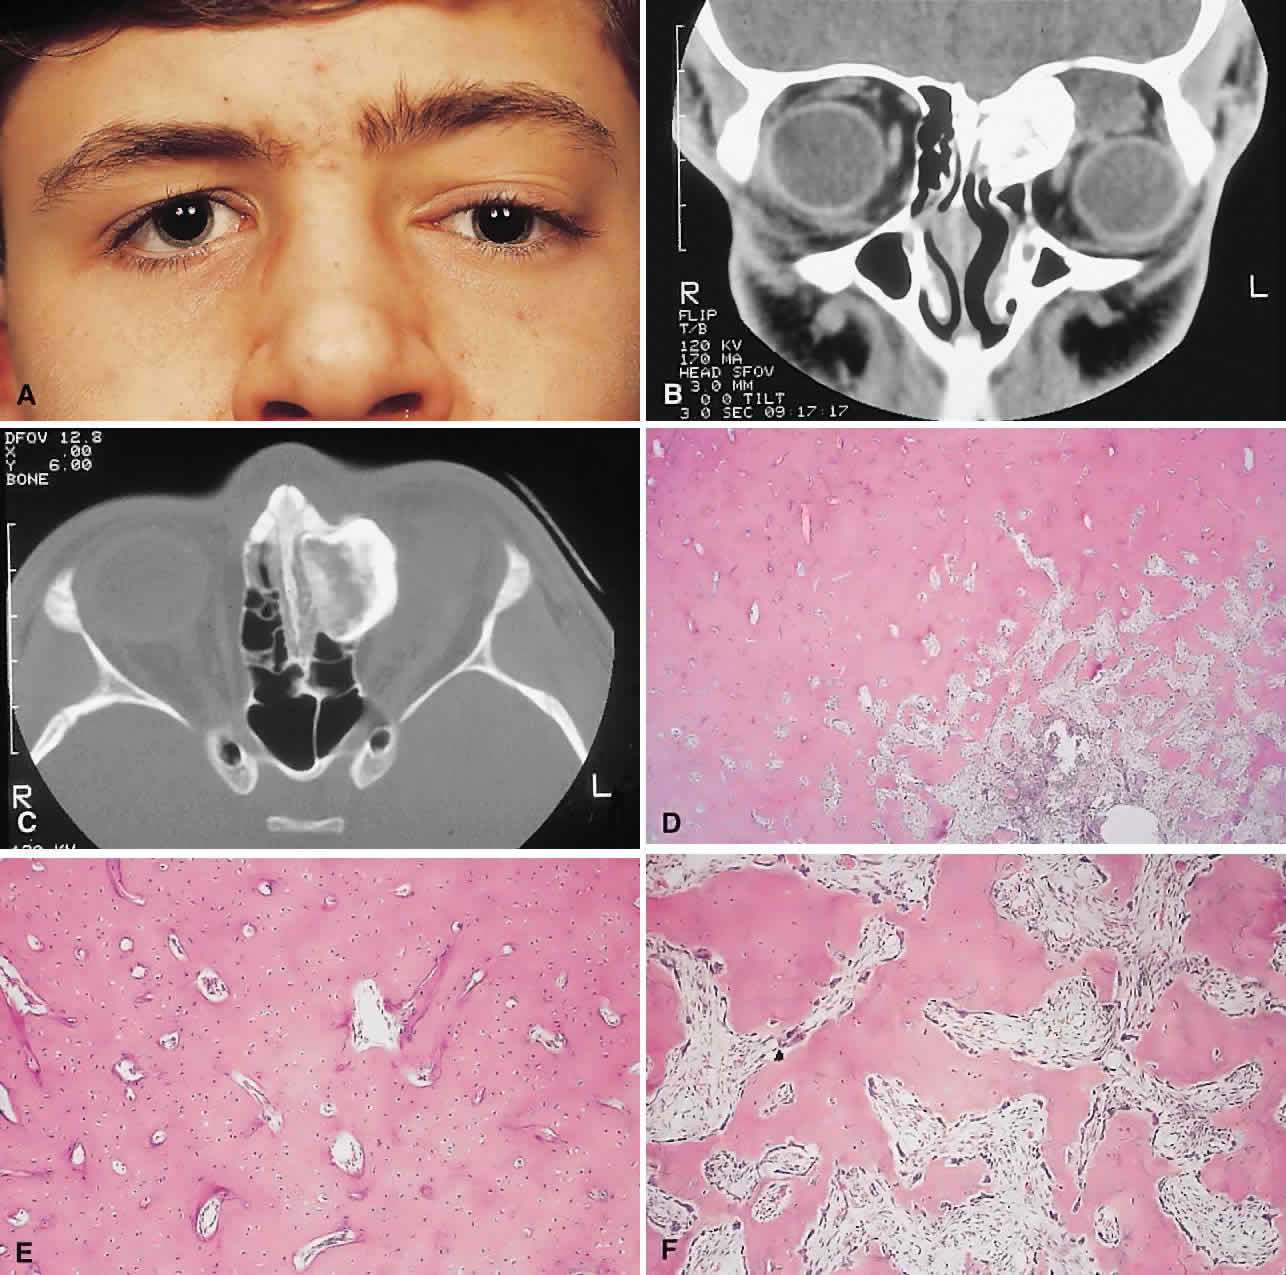

PRESENTATION. Most sinus osteomas are solitary and asymptomatic.6 However, when large enough to encroach on the orbits, a gradual evolution of proptosis or globe displacement over many years can occur (Fig. 1). There may be an associated headache as a result of expansion of the overlying cortex and periosteum, and a bony mass is often palpable in the superior or superomedial orbit. Obstruction of the sinus ostia may lead to chronic sinusitis or mucocele. Less common features include an acquired Brown syndrome,10 gaze-evoked amaurosis or pain,4,11 subluxation of the eye12 and erosion leading to orbital emphysema, or cerebrospinal fluid rhinorrhea.13 The sphenoid sinus, although a rare site, is significant because even a small lesion may lead to an orbital apex syndrome.

Fig. 1. A. A 15-year-old boy with a 10-month history of left proptosis had an inferolaterally displaced globe and 6 mm of proptosis. B. CT scan showed a circumscribed sclerotic mass arising from the frontoethmoidal area, with a frontal mucocele laterally. C. Bone windows revealed the bony mass to have a cancellous core and a sclerotic periphery. D. The histology showed a peripheral zone of compact bone, with increasing osteoblastic activity and fibrous tissue toward the center (hematoxylin-eosin, × 5). E and F. Higher power revealed areas of compact bone with haversian canals similar to normal cortical bone and regions of trabecular bone (F) with more osteoblastic activity present (hematoxylin-eosin, × 20).

IMAGING. The plain radiograph and CT appearances consist of an osteoblastic round or ovoid sharply circumscribed mass, usually arising in the sinus and invading the orbit. Tumors growing in a sinus conform to its internal contour and often have a bosselated surface. Osteomas may be sessile or pedunculated and generally have a diameter of 1 to 5 cm.18 Bone window settings on CT imaging often show a very dense periphery with a more cancellous internal structure. However, the relative proportions of the two densities may vary with the size of the lesion.

The compact areas resemble normal cortical bone with dense bony areas and haversian systems. However, there are subtle differences in the arrangement of the haversian canals, which is often evident to the experienced bone pathologist. The cancellous areas consist of anastomosing trabeculae with an intervening fibrovascular stroma. Fatty and hematopoietic elements may also be present in the stroma, as well as evidence of osteoblastic activity along the trabeculae. The fibrous region is made up primarily of loose fibrovascular tissue with a few irregular bony trabeculae and osteoid elements.

In our series of nine surgically treated cases, we noted that although the three types of tissue were present in varying admixtures, in all cases there was a remarkably consistent pattern of arrangement. The most peripheral zone was made up of compact bone; moving toward the center or base of the lesion, there was an intermediate zone of increased osteoblastic activity, osteoid, and vascularity. The innermost region consisted of a loose fibrous stroma with a greater number of blood vessels, few trabeculae, and many plump osteoblasts. This configuration has been described previously by Albert and associates20 and illustrates the growth of these lesions.

The outermost zone presumably represents more mature bone, and the activity seen centrally suggests that this is where growth is initiated. This implies that extirpation of the central region is probably required to prevent recurrence. It may also explain why leaving residual peripheral areas does not usually lead to regrowth.